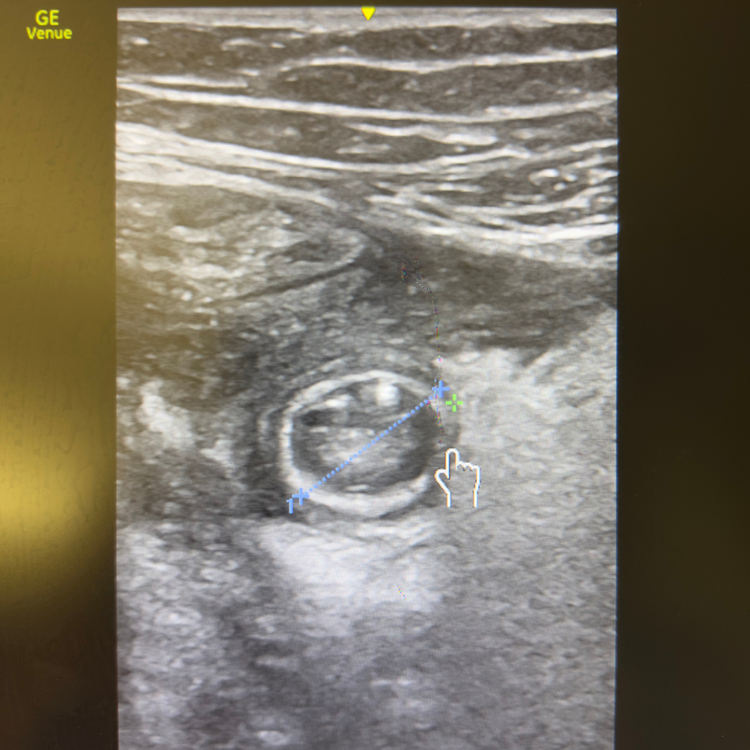

Confirmer la rétention en quelques secondes.